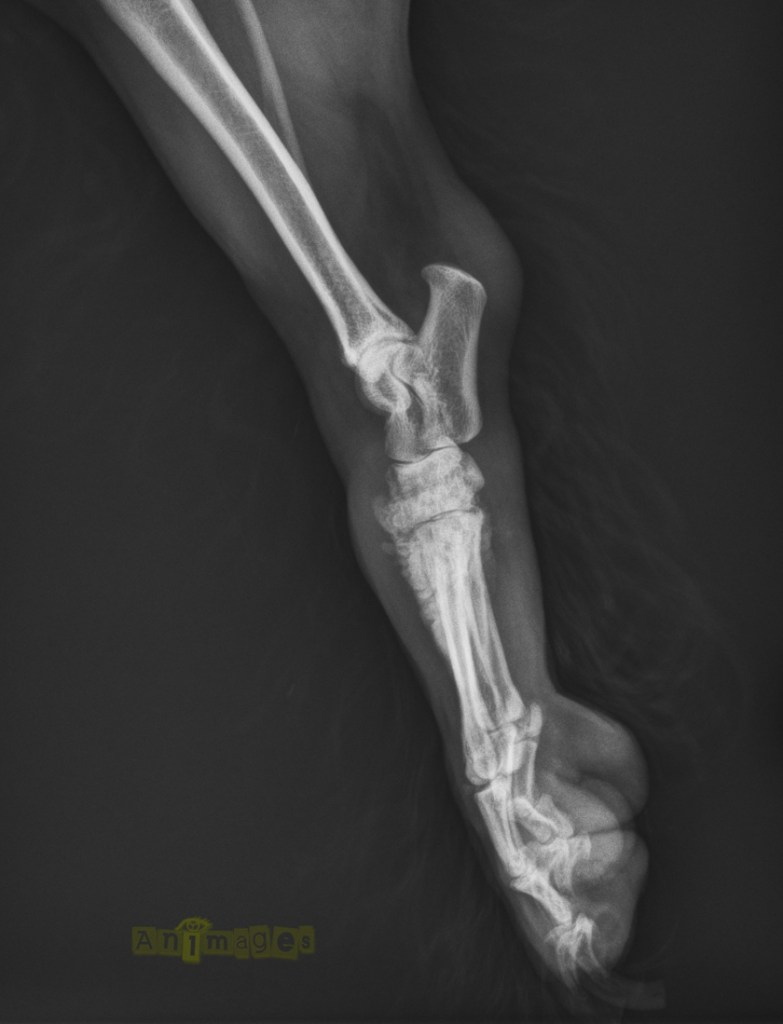

Latérale MPD